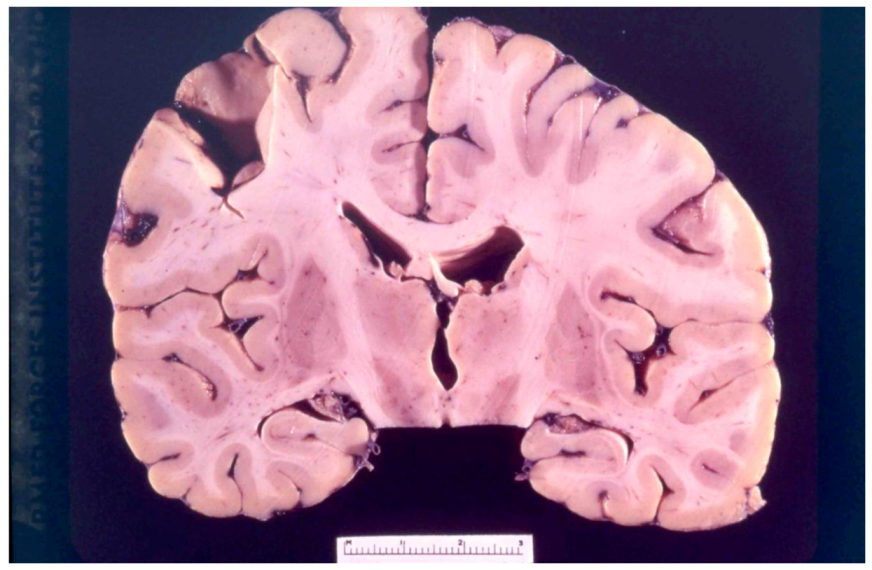

8. Neuropathology

- Klatzo, I.; Gajusek, D.C.; Zigas, V. Evaluation of Pathological Findings in Twelve Cases of Kuru. In Encephalitides; van Boagert, L., Radermecker, J., Hozay, J., Lowenthal, A., Eds.; Elsevier Publ. Comp.: Amsterdam, The Netherlands, 1959; pp. 172–190. [Google Scholar]

- Klatzo, I.; Gajusek, D.C. Pathology of kuru. Lab. Invest. 1959, 8, 799–847. [Google Scholar]

- Fowler, M.; Robertson, E.G. Observations on kuru. III: Pathological features in five cases. Australas Ann. Med. 1959, 8, 16–26. [Google Scholar]

- Kakulas, B.A.; Lecours, A.-R.; Gajdusek, D.C. Further observations on the pathology of kuru. J. Neuropathol. Exp. Neurol. 1967, 26, 85–97. [Google Scholar] [CrossRef]

- Neuman, M.A.; Gajdusek, D.C.; Zigas, V. Neuropathologic findings in exotic neurologic disorder among natives of the Highlands of New Guinea. J. Neuropathol. Exp. Neurol. 1964, 23, 486–507. [Google Scholar] [CrossRef]

- Liberski, P.P.; Sikorska, B.; Lindenbaum, S.; Goldfarb, L.G.; McLean, C.; Hainfellner, J.A.; Brown, P. Kuru: Genes, cannibals and neuropathology. J. Neuropathol. Exp. Neurol. 2012, 71, 92–103. [Google Scholar] [CrossRef]

- Hainfellner, J.; Liberski, P.P.; Guiroy, D.C.; Cervénaková, L.; Brown, P.; Gajdusek , D.C.; Budka, H. Pathology and immunohistochemistry of a kuru brain. Brain Pathol. 1997, 7, 547–554. [Google Scholar] [CrossRef]